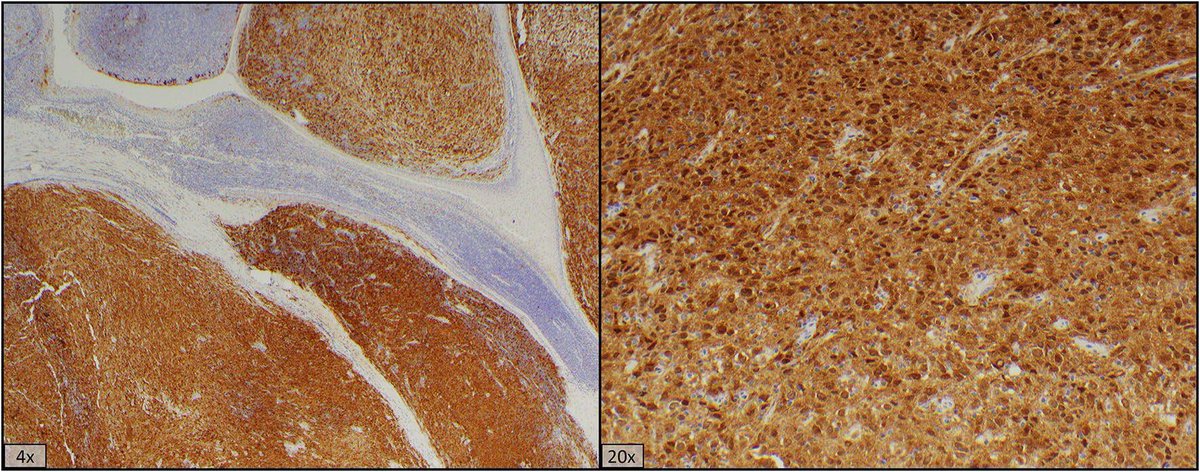

#MountaineerMonday case is a distal pancreatectomy from a young woman. The specimen showed a 5.4cm mass w/ findings consistent with Undif. Carcinoma w/ Osteoclast-like Giant Cells. Bone formation was present as well as a MCN component. #GIPath #pathology #usmle #medstudent